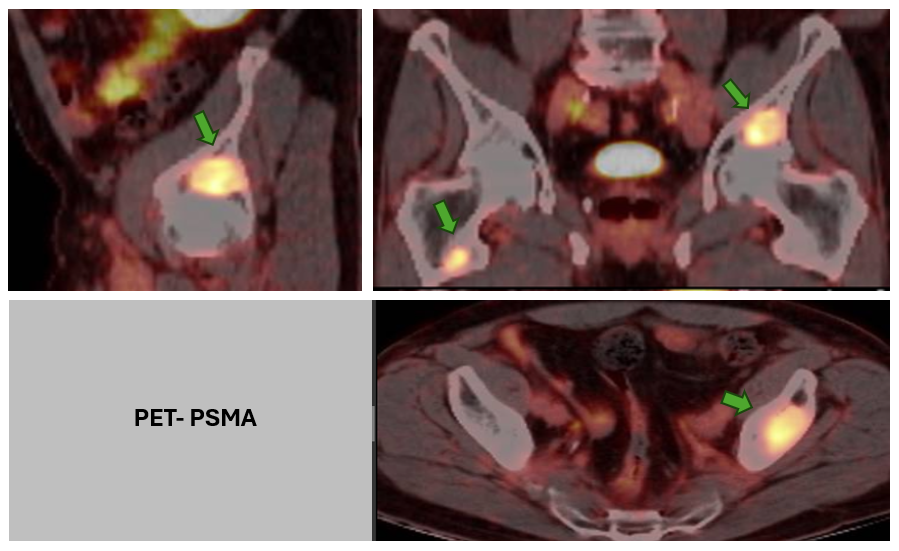

La técnica de PET-PSMA (Tomografía por Emisión de Positrones con trazadores dirigidos al PSMA) combina la imagen funcional propia del PET con un radiofármaco que se une específicamente a este antígeno. Esto permite localizar con gran precisión focos de enfermedad prostática activa, incluso en estadios donde otras modalidades de imagen como TAC o RMN podrían no ser concluyentes.

- Identificación de metástasis ocultas, tanto ganglionares como óseas, que pueden modificar radicalmente la estrategia terapéutica.

- Detección precoz de recurrencia bioquímica, incluso con niveles bajos de PSA.

- Evaluación objetiva de la respuesta a nuevas terapias, contribuyendo a definir criterios de eficacia basados en imagen funcional.